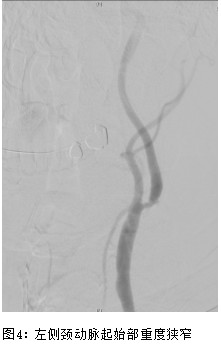

王先生,77岁,2月前无明显诱因出现头晕、黑矇、双下肢乏力,步行20余米需停下休息,1月前曾因下肢无力在家中摔倒1次,后于骑电动车途中摔倒1次。曾于外院输“活血”药物治疗,无明显好转。就诊于我院普内科,完善详细检查后考虑左侧颈动脉狭窄、脑梗。王老先生既往慢性疾病较多,15年前发现肺气肿、肺大疱及慢性支气管炎等慢性阻塞性肺病;2011年因急性心梗于行PCI术治疗,植入2枚支架,近期偶有心绞痛发作;同时还有高血压、慢性肾功能不全等疾病。术前超声造影提示:左侧颈动脉重度狭窄,局部峰值流速约200cm/s,斑块可见较多造影剂微气泡及细线样灌注;考虑为不稳定斑块。因患者心肺肾等重要脏器功能欠佳,无法耐受颈动脉内膜剥脱手术,经多学科MDT讨论评估后决定行微创颈动脉支架治疗;赵克强副主任医师在局麻下为王先生进行了微创颈动脉支架手术,40分钟内手术顺利结束,仅仅用了不到50ml造影剂,避免肾功能的进一步恶化,术后3天康复出院。术后随访期间老王未再次出现头晕、黑矇等TIA发作表现。